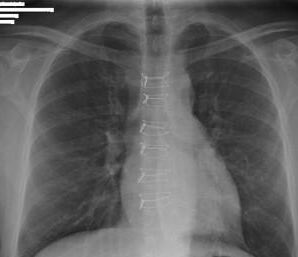

شرايكم نشوف الاكس راي مره الثانيه 🙊